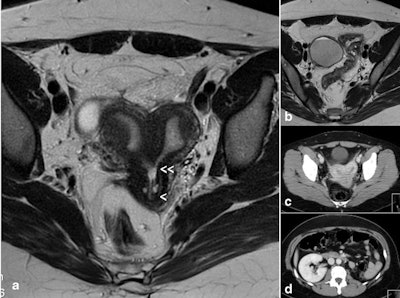

For instance, in cases of agenesis or hypoplasia of a urogenital ridge, there will be the absence of the kidney, ureter, ovary, fallopian tube, hemiuterus, and hemivagina. Clinically, the most common presentation is a unicornuate uterus without a rudimentary horn or contralateral tube and ovary, the researchers found.

MRI is the best modality for imaging these malformations, complemented with hysterosalpingography if unicornuate uterus is present.

The combination of uterine duplicity and obstructed or blind hemivagina appears to be virtually always associated with ipsilateral renal agenesis or dysgenesis, and imaging tests are necessary to confirm the absence of a normal kidney on the affected side and also to detect abnormalities of the contralateral kidney and ureter, they added.

If there is unilateral renal agenesis, there must also be genital malformation with didelphys, bicornuate, and, more rarely, septate uterus (sometimes reported as single uterus), but not necessarily a blind or atretic hemivagina. There could also be cases with partial reabsorption of the vaginal septum, they continued.